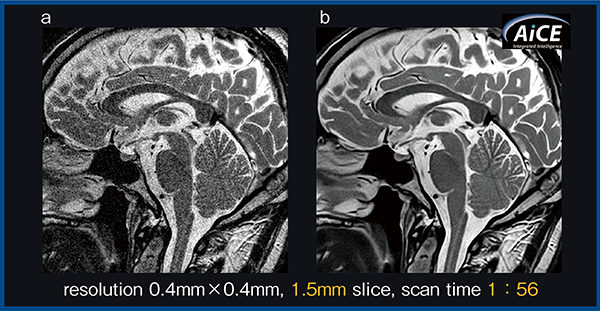

また,図3はAiCEを高分解能化に活用した例である。スライス方向の分解能を向上させて下垂体病変でのパーシャルボリューム効果の低減を図り,2分以内の撮像時間で高画質の画像が得られた(b)。

図3 AiCEによる高分解能撮像(下垂体)